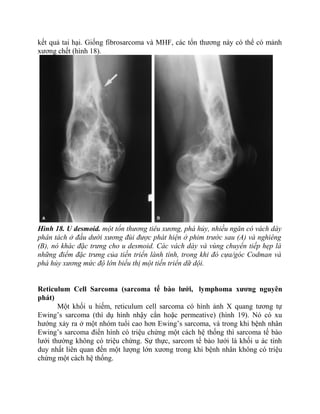

Desmoid (u xơ)

Một khối u desmoid (đừng nhầm với cortical desmoid) là một fibrosarcoma

bán cấp (half-grade). Nó còn được gọi là desmoplastic fibroma hay aggressive

fibromatosis. Những tổn thương này, giống fibrosarcoma, là tiêu xương nhưng

thường có ranh giới khá rõ do sự phát triển chậm của chúng. Chúng thường có

phản ứng màng xương lành tính với các gai dày hay “spikes”, và bình thường có

hình nhiều ngăn với vách dày (hình 18). Chúng phát triển chậm và hiếm khi di căn,

nhưng chúng có thể lan rộng không thể ngăn cản vào mô mềm xung quanh với các

kết quả tai hại. Giống fibrosarcoma và MHF, các tổn thương này có thể có mảnh

xương chết (hình 18).

Hình 18. U desmoid. một tổn thương tiêu xương, phá hủy, nhiều ngăn có vách dày

phân tách ở đầu dưới xương đùi được phát hiện ở phim trước sau (A) và nghiêng

(B), nó khác đặc trưng cho u desmoid. Các vách dày và vùng chuyển tiếp hẹp là

những điểm đặc trưng của tiến triển lành tính, trong khi đó cựa/góc Codman và

phá hủy xương mức độ lớn biểu thị một tiến triển dữ dội.

Reticulum Cell Sarcoma (sarcoma tế bào lưới, lymphoma xương nguyên

phát)

Một khối u hiếm, reticulum cell sarcoma có hình ảnh X quang tương tự

Ewing’s sarcoma (thí dụ hình nhậy cắn hoặc permeative) (hình 19). Nó có xu

hướng xảy ra ở một nhóm tuổi cao hơn Ewing’s sarcoma, và trong khi bệnh nhân

Ewing’s sarcoma điển hình có triệu chứng một cách hệ thống thì sarcoma tế bào

lưới thường không có triệu chứng. Sự thực, sarcom tế bào lưới là khối u ác tính

duy nhất liên quan đến một lượng lớn xương trong khi bệnh nhân không có triệu

chứng một cách hệ thống.